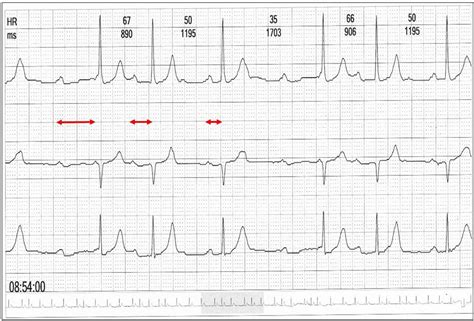

The Wenckebach block ECG is characterized by a progressive prolongation of the PR interval on the electrocardiogram until a beat is dropped. The PR interval represents the time it takes for the electrical impulse to travel from the atria to the ventricles. In Wenckebach block, this interval gradually increases with each successive beat until the AV node completely blocks an impulse, resulting in a missing QRS complex. After the dropped beat, the PR interval resets and the cycle begins again. This repeating pattern of progressive PR interval lengthening followed by a dropped beat is the hallmark of Wenckebach block, making it a relatively easy rhythm to identify once you know what to look for. It’s also important to note that the R-R interval (the time between ventricular beats) shortens slightly before the dropped beat, creating a grouped beating pattern. Understanding these key characteristics is crucial for accurate diagnosis and appropriate management of this type of heart block. Wenckebach block can occur due to various reasons, including increased vagal tone, certain medications, or underlying heart conditions, highlighting the importance of thorough clinical evaluation to determine the underlying cause and guide treatment decisions. Recognizing Wenckebach block on an ECG is a fundamental skill for healthcare professionals, as it enables timely intervention to prevent potential complications associated with this arrhythmia. By familiarizing themselves with the distinctive ECG features of Wenckebach block, clinicians can confidently identify and manage this condition, ultimately improving patient outcomes. Overall, Wenckebach block represents a fascinating and clinically significant cardiac arrhythmia that warrants careful attention and understanding. Its unique ECG pattern provides valuable insights into the underlying electrical conduction abnormalities within the heart, allowing for targeted diagnostic and therapeutic interventions. With a comprehensive grasp of Wenckebach block, healthcare providers can deliver optimal care to patients affected by this condition.

• Progressive PR Interval Prolongation: This is the big one. The PR interval, which represents the time it takes for the electrical impulse to travel from the atria (upper chambers) to the ventricles (lower chambers), gradually gets longer with each beat. It’s like the AV node is getting more and more tired, delaying the signal a little bit more each time. You’ll see the PR interval slowly creeping upwards on the ECG strip.

• Dropped Beat (QRS Complex): Eventually, the AV node gets so fatigued that it completely blocks an electrical impulse from reaching the ventricles. This results in a missing QRS complex – the part of the ECG that represents ventricular contraction. It’s like the heart skips a beat!

• R-R Interval Shortening: Before the dropped beat, you might notice that the R-R interval (the distance between two consecutive R waves, representing ventricular beats) actually shortens slightly. This is because the progressive prolongation of the PR interval is occurring within that R-R interval, effectively squeezing it a bit.

• Pattern Repetition: The most important thing is that this pattern repeats itself! You’ll see the progressive PR prolongation, the dropped beat, and then the whole cycle starts again. This repeating pattern is what makes Wenckebach so recognizable on an ECG. Think of it as a predictable dance of electrical signals.

When you’re looking at an ECG, focus on meticulously measuring the PR intervals across several beats. Do you observe a gradual increase in duration, followed by a sudden absence of a QRS complex? If so, you’re likely looking at Wenckebach. The ratio of P waves to QRS complexes is also important. Because of the dropped beat, you’ll have more P waves than QRS complexes. For example, you might see a 3:2 or 4:3 ratio, meaning there are three or four P waves for every two or three QRS complexes. The P waves themselves usually look normal, because the problem is in the AV node, not in the atria. After the dropped QRS complex, the PR interval resets and the cycle begins anew. This reset is a key feature that differentiates Wenckebach from other types of heart block. Also, it’s important to rule out other possible causes of dropped beats, such as premature atrial contractions (PACs) that are blocked in the AV node. However, PACs typically don’t show the progressive PR interval prolongation that’s characteristic of Wenckebach. Recognizing these subtle but critical distinctions is essential for accurate ECG interpretation and appropriate clinical management. Always correlate the ECG findings with the patient’s clinical presentation. Some individuals with Wenckebach block may be asymptomatic, while others may experience dizziness, lightheadedness, or even syncope (fainting). The severity of symptoms often depends on the heart rate and the frequency of dropped beats. In asymptomatic cases, treatment may not be necessary, but regular monitoring is advisable. In symptomatic cases, treatment options may include medications to increase heart rate or, in severe cases, a pacemaker to ensure consistent ventricular pacing. Overall, mastering the art of identifying Wenckebach block on an ECG requires a keen eye for detail, a thorough understanding of cardiac electrophysiology, and a commitment to continuous learning. By honing your ECG interpretation skills, you can play a vital role in the early detection and management of this important cardiac arrhythmia.